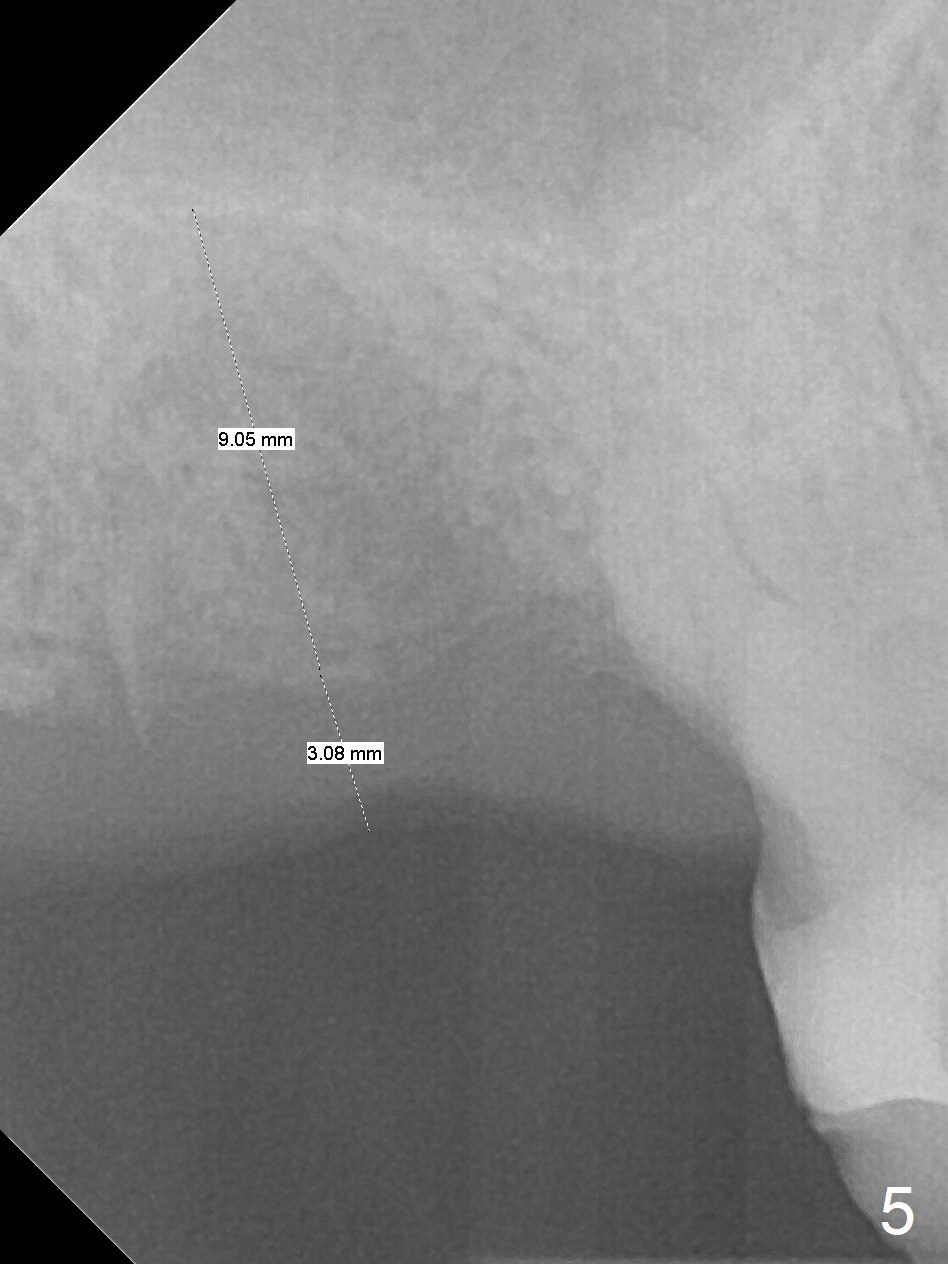

A 65-year-old man returned to finish LR and LL quadrant SRP a few weeks post SRP for UR quadrant and #2 extraction (Fig.1-2). He returns for UL SRP tomorrow ~ 3 months post extraction (Fig.4). Although the patient cannot remember whether socket preservation is done or not, there appears to be bone graft in the socket. The ridge is wide. It seems reasonable to expand and condense the socket using Magic Split and Expanders (flapless). If the patient cannot tolerate tapping, use DIO Bone Expanders. A 6.5x9 (3) mm Magicore will be placed (Fig.5,6).